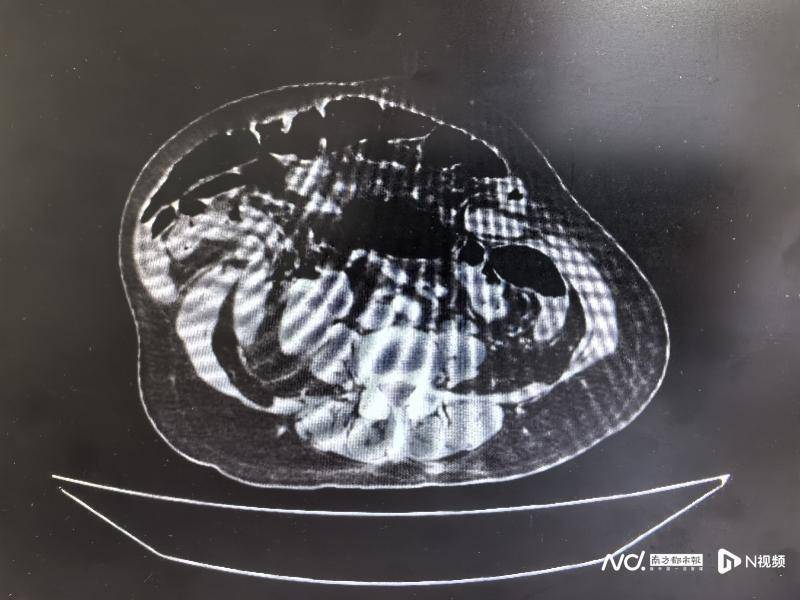

两年前,七旬老人张阿姨因多次腹部手术后腹壁形成长达31厘米的切口疝,肠管、胃等脏器“越狱”脱出腹腔外,在皮下形成“第二腹腔”生活备受影响。经暨南大学附属第一医院疝与腹壁外科团队多学科协作,最终成功修复